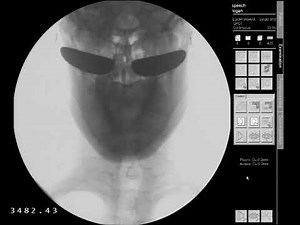

Vfss - Normal

Videofluoroscopy - Normal

Videofluoroscopy - Barium Swallow